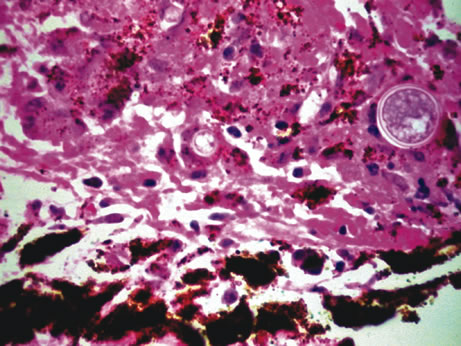

Necrotizing retinitis with secondary choroiditis is seen in protozoal infections such as toxoplasmosis or in herpetic infections. Infection with Toxoplasma gondii leads to retinitis and secondary choroiditis (Fig. 25), usually granulomatous.127 Congenital infection can be acquired in utero by transplacental transmission of the parasite from the infected mother to the fetus.128 Acquired disease occurs after ingestion of oocysts or tissue cysts.129–132 The congenital form of infection leads to atypical macular colobomas. Reactivation of the infection is caused by release of organisms that have remained dormant in the margins of old congenital retinal scars.133 The slowly proliferating form of the organism, termed the bradyzoite, can be seen in cysts. The rapidly multiplying form, termed the tachyzoite, may be difficult to identify in an infected retina or in immunocompetent individuals, but they are frequently seen in the retinitis of immunocompromised hosts.134 Active infection usually causes focal retinal opacification and an intense vitritis. These findings may give the appearance of a “headlight in a fog” in an immunocompetent person. In contrast, this clinical presentation is rare in patients with AIDS, in whom diffuse retinitis is observed with non-granulomatous choroiditis.134

Fig. 25. Toxoplasma retinochoroiditis. Necrotic retina shows cysts of toxoplasma gondii, and the choroid reveals granulomatous inflammation. (Hemotoxylin-eosin ×65.) Inset (Gomori methenamine silver ×160) shows cysts of the organisms.